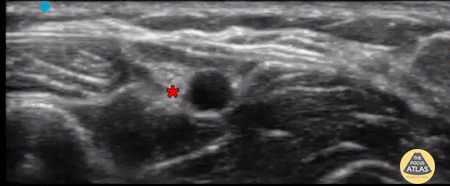

Radial Nerve Block Performed for wound exploration and laceration repair of a 1.5cm laceration located at the radial aspect of the forearm, proximal 4cm from the radial styloid. The nerve was identified as a heterogenous hyperechoic structure lateral to the radial artery and superficial to the radius. Located superior is the extensor carpi radialis longus and brevis muscle. Hydrodissection was performed in-plane using a 22-gauge needle with 5mL of 1% lidocaine without epinephrine. Submitted by Dr. Spencer Kim and Dr. Maurelus, Kings County Medical Center